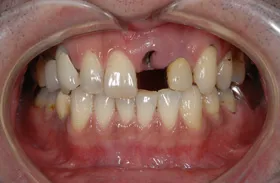

生まれつき歯が生えてこなかったケース

■治療前:生まれつき下顎左右前歯がなく隙間がある

■治療後:矯正治療後、下顎左右3番の2本にインプラント治療

| 主訴 | 生まれつき歯がなく隙間があり、審美障害・咀嚼機能障害がある |

| 治療方法 | インプラント治療 + 矯正治療 |

| 治療期間 | インプラント治療 約6ヶ月 |

| 通院回数等 | インプラント治療 約6回 |

| 費用 | 約94万円(税込) |

| リスク・副作用 | 術後の腫れ・痛み |